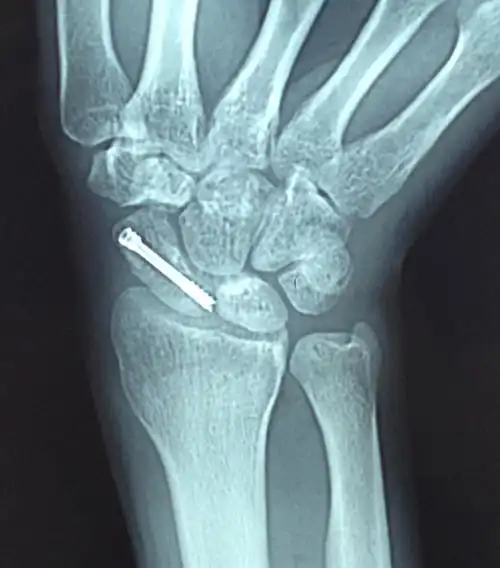

透视下herbert钉固定舟状骨骨折,关节镜下探查桡腕关节及腕中关节

腕舟骨骨折

dr,ct检查后诊断:右腕舟骨骨折.